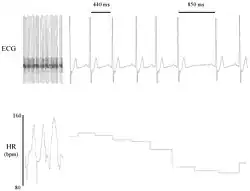

Heart rate variability visualized with R-R interval changes

Electrocardiogram (ECG) recording of a canine heart that illustrates beat-to-beat variability in R–R interval (top) and heart rate (bottom).